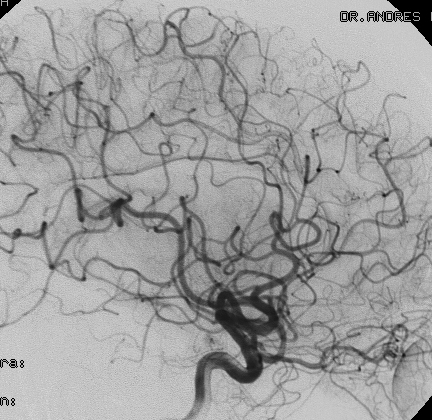

Angiografía 7 años después de la embolización mostrando reducción importante y definitiva del volumen de la MAV, convirtiéndola en blanco óptimo para radiocirugía

Al cabo de 18 meses de la radiocirugía la MAV está curada sin efectos adversos ni secuelas. El paciente continuó su trabajo e incluso estudios de post grado.